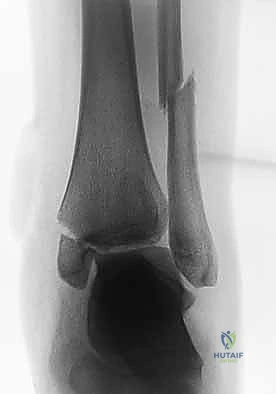

2. الأشعة السينية (X-rays)

هي الخطوة الأساسية. يتم أخذ صور بأوضاع مختلفة (أمامي، جانبي، ومائل - Mortise view) لتحديد مكان الكسر، درجة التفتت، ومدى تباعد العظام.